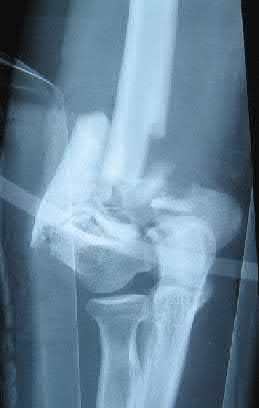

Question 11:

Correct Answer: Greater trochanters

Explanation:

For optimal mechanical advantage and effective reduction of an 'open book' pelvic fracture (APC type), a pelvic binder must be applied directly over the greater trochanters of the femurs. Applying it higher, such as over the iliac crests, is a common error that fails to adequately close the pelvic ring and can paradoxically open the true pelvis.